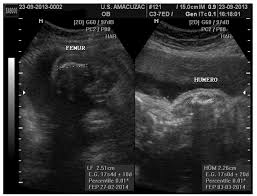

Mide la longitud del fémur el hueso del muslo y se expresa en milímetros. Por sunnyfunny Mié Oct 08 2008 859 pm. LF en español es longitud del fémur expresada en milímetros.

COLUMNA CORAZON DE 4 CAMARAS. Y biometría fetal secundaria a la medición del diámetro cerebeloso transverso DCT longitud renal LR y longitud del pie LP. Diámetro biparietal de un lado a otro de la cabeza expresado en milímetros.

Biometria Iii Longitud De Femur Lf